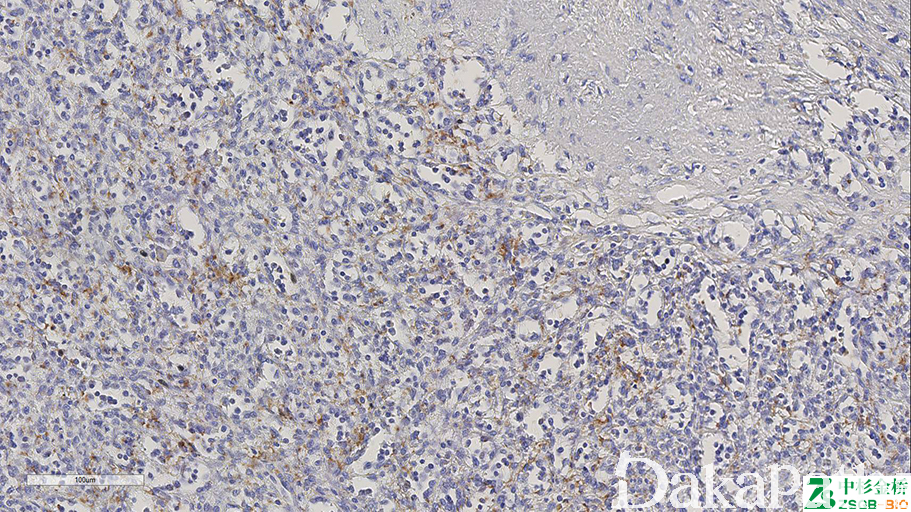

CD61

别名: integrin beta 3 chain (ITGB3)、GPIIIa

与 CD41 结合形成血小板糖蛋白 Iib/IIIa 复合体,参与凝血及血栓形成。骨髓巨核细胞及血小板的标记物,也可标记髓系、内皮细胞等。对过度脱钙敏感,可以作为脱钙程度的内参。

信号定位: 胞膜、胞浆